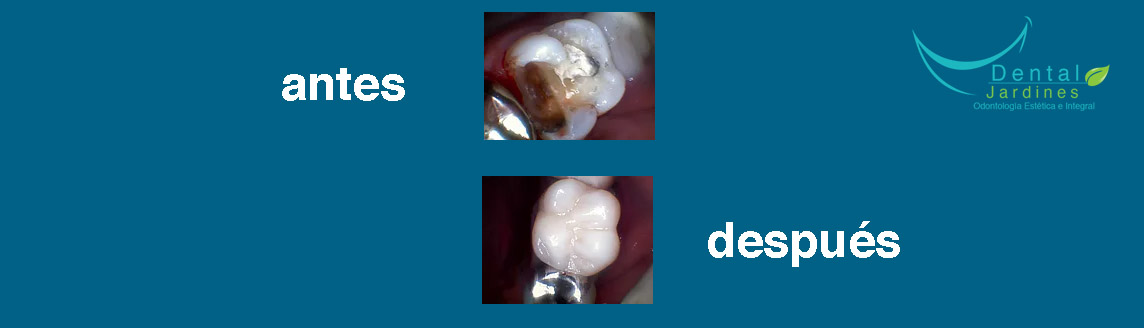

Nuestro objetivo principal es la calidad en nuestros tratamientos por lo cual te ofrecemos una consulta en la cual se te dará el tiempo suficiente para que el procedimiento tenga el mejor resultado. Nuestros tratamientos llevan un registro radiológico y fotográfico para que puedas observar el cambio en una foto de antes y después para lograr la satisfacción de nuestros pacientes.